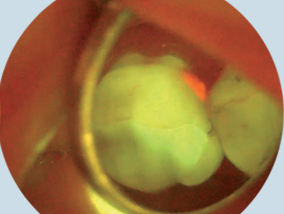

caries-fluorescence

• Fluorescence and transillumination technology have been proven successful in identifying soft and hard tissue abnormalities.

• DOE Oral Exam System provides dentists an X-ray vision to easily identify abnormal tissue that might develop into oral cancer or dental caries through the contrast of green healthy fluorescence and dark abnormal tissue.

• It is pleasant and fast with no need of rinsing the mouth.